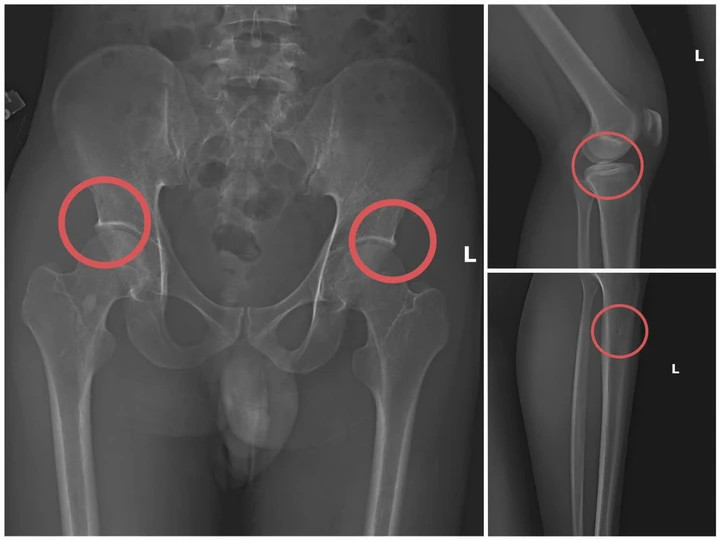

Bản phim chụp XQ một số tổn thương xương do đối tượng tạo ra nhằm trục lợi tiền bảo hiểm nhân thọ.

Theo Công an tỉnh Phú Thọ, đường dây trục lợi bảo hiểm bằng thủ đoạn tự đục vỡ xương khớp nhằm tạo thương tích giả do Tạ Minh Châu (SN 1996), nguyên cán bộ Trung tâm Y tế huyện Cẩm Khê cầm đầu.

Lợi dụng thời gian dài công tác trong ngành và am hiểu cấu trúc xương, khớp, Châu đã xây dựng quy trình trục lợi theo chuỗi khép kín gồm: Vận động người mua bảo hiểm nhân thọ, trực tiếp gây thương tích bằng thuốc mê và các dụng cụ tác động lực, sau đó dựng hiện trường giả để hợp thức hóa hồ sơ điều trị.

Đáng chú ý, Châu trực tiếp thực hiện hành vi tiêm thuốc mê rồi dùng kim tiêm, búa để tác động vào xương người mua bảo hiểm, tạo nên các vết vỡ xương tương tự tai nạn thật. Khi thương tích đã tạo xong, Châu tiếp tục hướng dẫn các đối tượng dựng hiện trường giả như điện giật ngã, trượt chân ngã suối nhằm hợp thức hóa bệnh án và hoàn thiện hồ sơ yêu cầu chi trả.